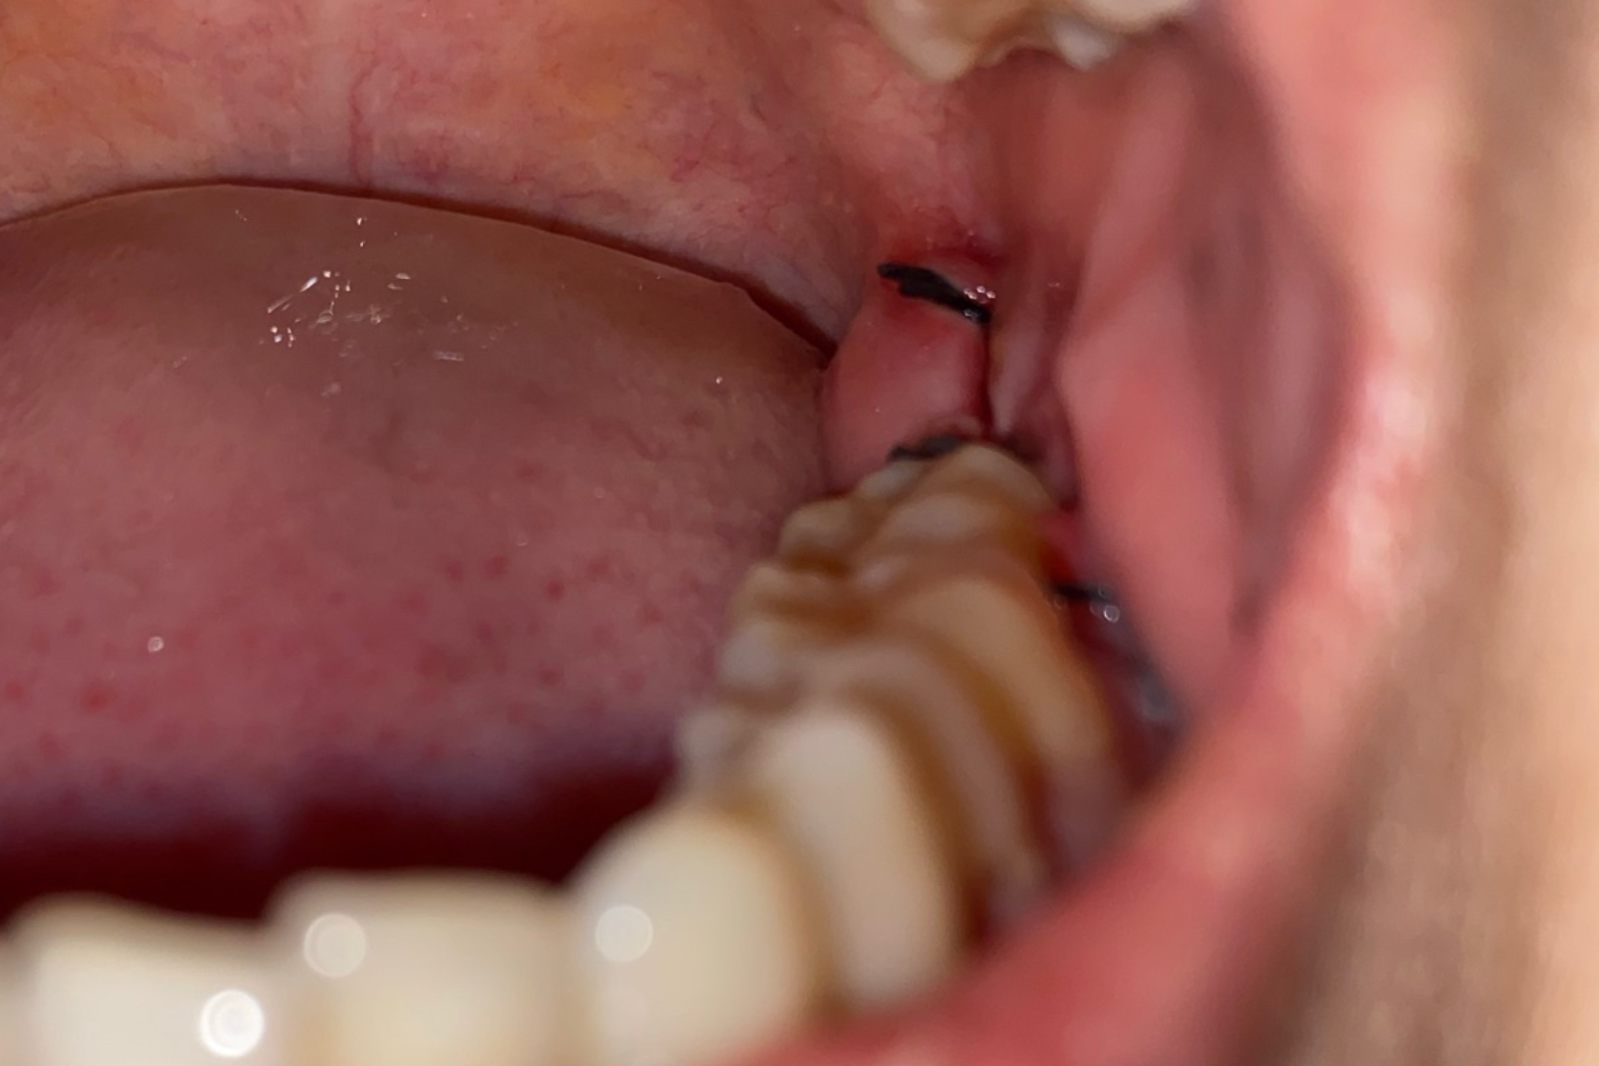

拔除智齿后三天的正常伤口,局部出血的现象应得到明显改善,且局部肿胀、疼痛的现象也应有所缓解。多数人在拔出智齿三到五天左右,伤口就会慢慢愈合。

拔除智齿三天后,正常的伤口多不会再流血,伤口会被凝血块所封闭,但极少数患者可能还会出现轻微的局部肿胀、疼痛的现象。